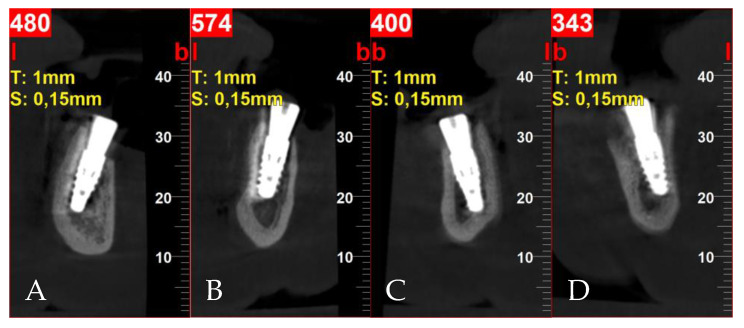

Postoperative cross-sectional CBCT scans: (A) tooth 32; (B) tooth 34; (C) tooth 42; (D) tooth 44.